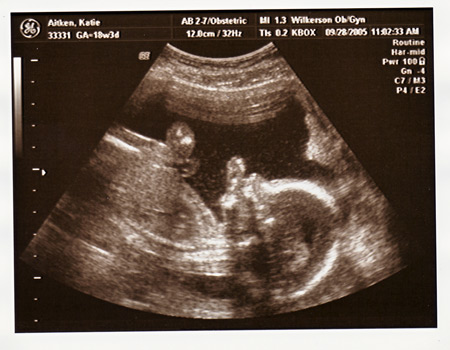

I had my ultrasound today, and found out everything is perfect and in place. We are so excited that Maeve will have a little sister to play with!!!

Here is Maeve's sonogram, from when she was the same gestational age: